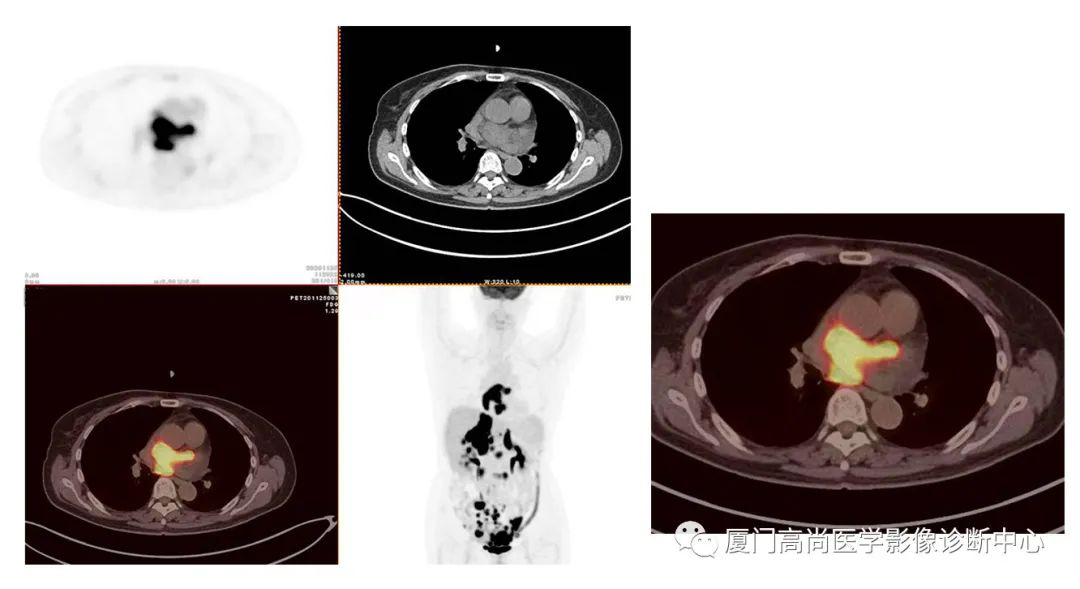

病例1:某男士,36歲,半年前摔傷,當(dāng)時(shí)無大礙,近幾個(gè)月來腰腿痛,并逐漸加重,消瘦10多斤。MRI檢查發(fā)現(xiàn)腰椎、骨盆 骨質(zhì)異常信號(hào),查血各項(xiàng)腫瘤標(biāo)記物正常,因診斷不清而來做PET/CT檢查

淋巴瘤在骨骼、肝臟、脾臟、淋巴結(jié)表現(xiàn)

肝臟、脾臟、骨骼淋巴瘤病灶

PET/CT發(fā)現(xiàn) :全身多發(fā)淋巴結(jié)腫大,F(xiàn)DG攝取增高;肝臟、脾臟多發(fā)低密度結(jié)節(jié), FDG攝取增高;雙側(cè)扁桃體腫大,F(xiàn)DG攝取增高;全身多處骨骼破壞,F(xiàn)GD攝取增高;上述考慮為淋巴瘤

經(jīng)淋巴結(jié)穿刺活檢 :病理診斷為彌漫大B細(xì)胞淋巴瘤